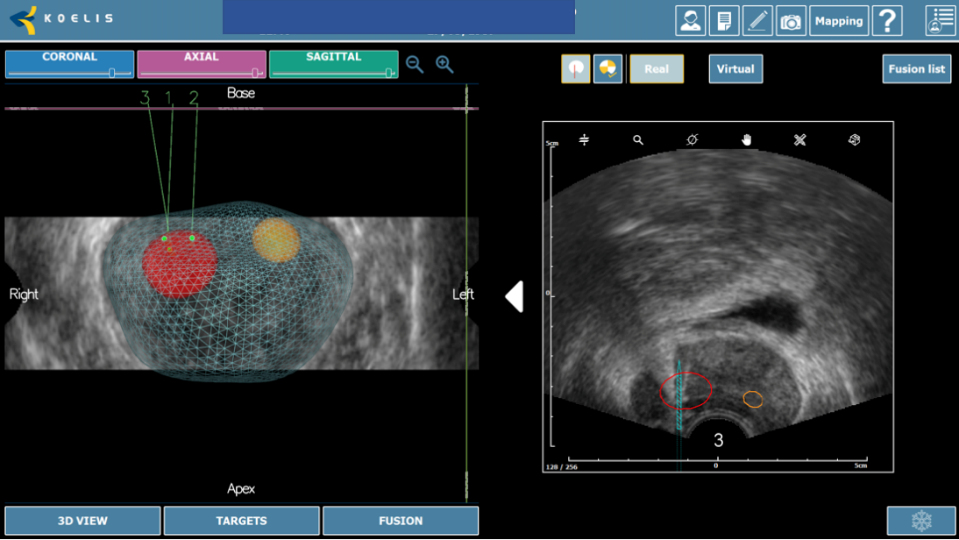

La próstata se escanea con la sonda de US. El operador define los contornos de la próstata y delinea las lesiones sospechosas a tratar en las imágenes de Resonancia. Los límites de la próstata se definen en la imagen en tiempo real de la próstata obtenida con la sonda trans-rectal del dispositivo. El software ejecuta automáticamente una “fusión elástica” de los dos volúmenes definidos, lo que conduce a una combinación tridimensional (3D) perfecta del volumen de RM con el volumen de la próstata en US. La misma fusión 3D se aplica al área sospechosa previamente identificada en la resonancia magnética y/o Biopsia por fusión que, por lo tanto, se puede identificar correctamente en la imagen en vivo de US. (Figura 3-4).

La terapia focal permite la preservación de la mayoría de tejido prostático normal, incluyendo los haces neurovasculares y mecanismos de la continencia urinaria. Adicionalmente, los avances en mpMRI y los mapas de Biopsias por fusión, definen precisamente la lesión objetivo y usando HIFU uno puede tratar solamente esa lesión o esa área a fin de mantener un margen de seguridad oncológica (Figura 4).

A diferencia de un tratamiento total, la hemi-ablación es la ablación de la mitad de la próstata, donde se encuentra el tumor, esta es la estrategia más utilizada en la actualidad. (Figura 6).